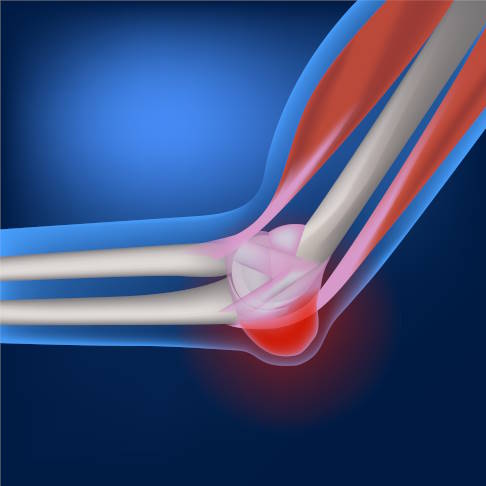

Schleimbeutelentzündung am Ellenbogen

Im Ellenbogen liegt der Schleimbeutel an der Außenseite des Gelenks. Die häufigsten Ursachen für Schleimbeutelentzündungen am Ellenbogen sind Unfälle oder Prellungen. Hieraus kann sich sogar eine chronische Bursitis entwickeln. Als weitere Auslöser gelten Druckbelastungen und Überbeanspruchung. Schwellung, Überwärmung, Bewegungseinschränkungen und Ellenbogenschmerzen sind typische Symptome.